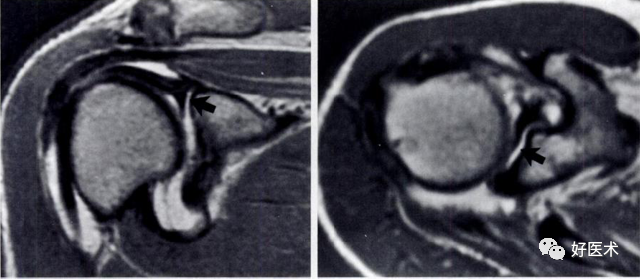

3)完全性撕裂

原发征象:肌腱局部缺如,连续性液体信号横贯肌腱的全层,这使得盂肱关节和肩峰下滑囊相通。

继发征象:

①肩峰下滑膜囊积液,积液在T1WI /PDWI上呈中等信号,T2WI+FS上呈高信号;

②冈上肌肌肉、肌腱结合处回缩(正常位置在肱骨头上方);

③滑囊旁脂肪垫的渗出丢失。

MR 关节造影:局限性或弥漫性充满造影剂的裂隙贯穿肌腱全层,肌腱失去其连续性。

冈上肌腱不完全撕裂

冈上肌腱不完全撕裂伴肩峰下囊积液